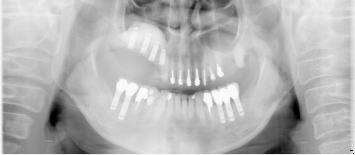

47歳女性

ブリッジや義歯でも可能な症例ですが、残っている歯を守りたいという患者さんの希望によりインプラント施術。

なお、この患者さんは歯医者の方で、専門知識の高い歯科医師の方にも喜んでもらえて大変光栄でした

術前

↓↓↓↓

術後